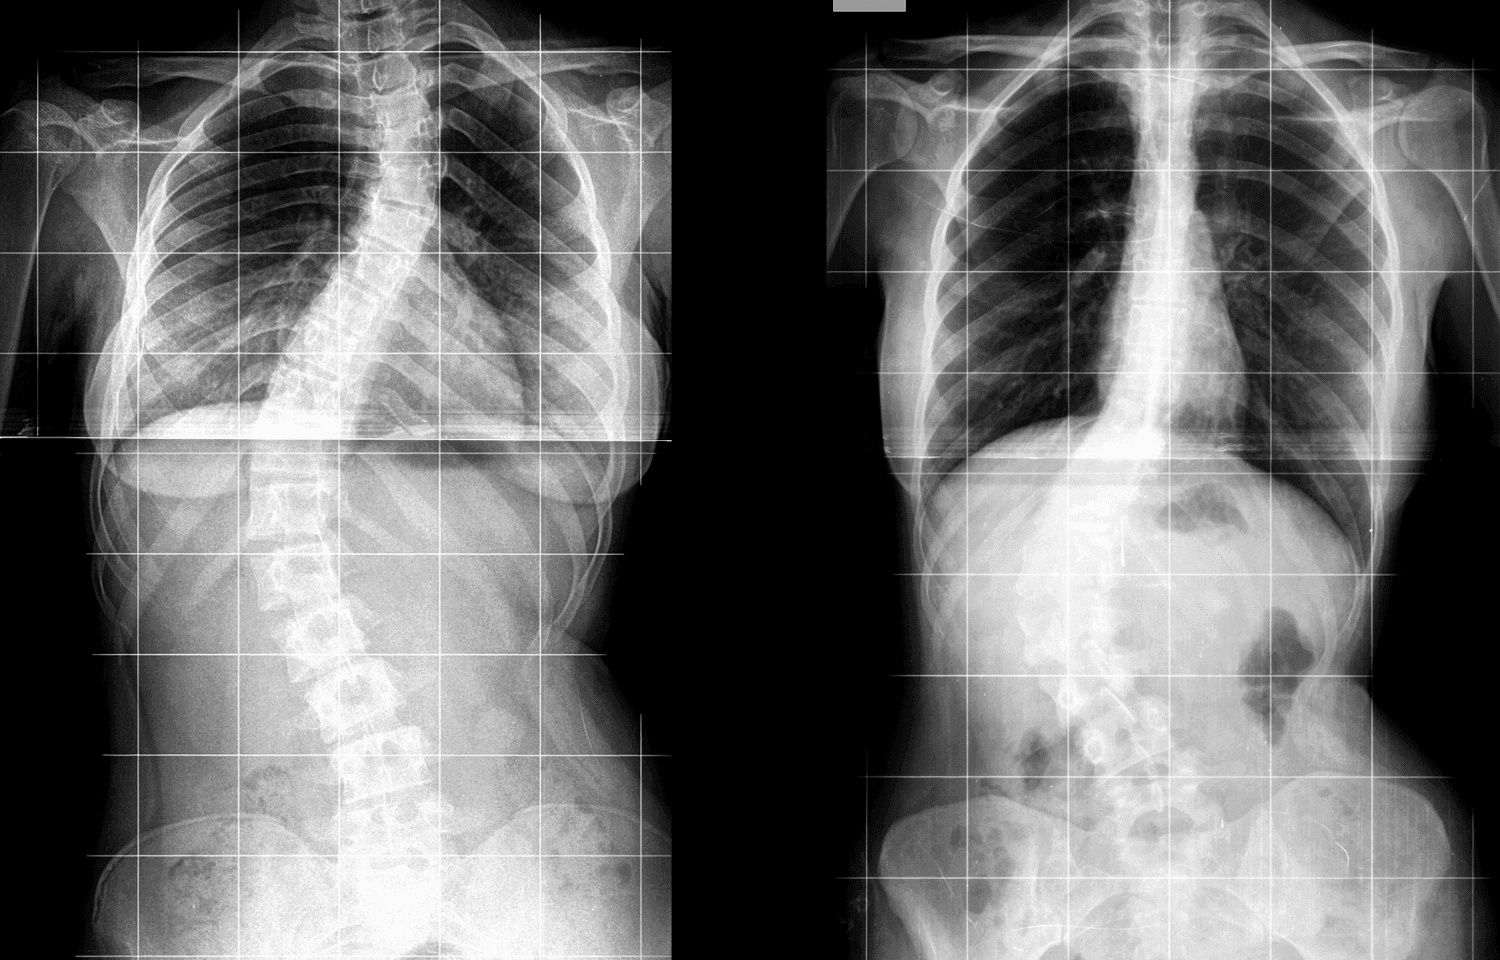

Röntgen görüntüleri, kemik ve eklem yapılarının detaylı incelenmesini sağlayarak bu süreçte kritik bir rol oynar. Röntgen, basit ve hızlı uygulanabilir bir görüntüleme yöntemi olarak birçok alanda değerlendirilir.

Röntgen Kullanım Alanları:

- Doğumsal anomalilerin teşhisi

Röntgen görüntülerinin doğru okunması, tedavi planlamasında hataları en aza indirir ve uygun cerrahi veya konservatif tedavi yöntemlerinin belirlenmesini sağlar.

Yanlış veya eksik röntgen yorumlanması, doğru olmayan bir tanıya ve devamında uygunsuz bir tedaviye yol açabilir. Bu durum, hastanın iyileşme sürecini uzatabilir ve hatta kalıcı hasarlara neden olabilir. Bu nedenle, ortopedi ve travmatoloji uzmanlarının röntgen görüntülerini doğru yorumlaması hayati öneme sahiptir.